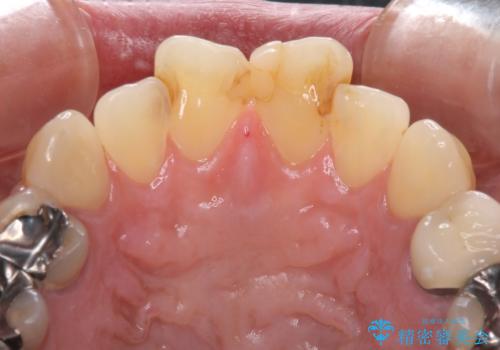

- 何度もコンポジットレジンによる修復を繰り返した結果、冷たいものがしみるようになってしまったとのことで来院された患者様です。

前歯2本が捻れている形態も気になるとのことであったので、虫歯の治療を兼ねて、オールセラミッククラウンにて補綴治療を行うこととしました。

2本とも治療前の歯髄の状態は正常でしたが、補綴治療により歯を大きく削ることになるため、歯髄が炎症を起こすリスクがあることを了解いただきました。